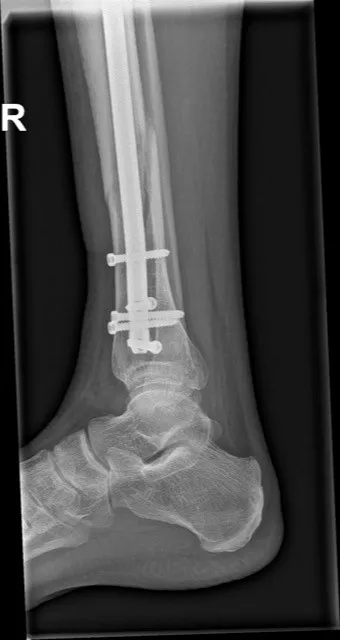

Stap 3: Operatieve behandeling: bij een verplaatste of instabiele onderbeenfractuur is een operatie vrijwel altijd nodig. De orthopedisch chirurg zet tijdens de operatie de botdelen weer passend op elkaar en stabiliseert de breuk. Vaak gebeurt dit met een metalen nagel in het scheenbeen (intramedullaire nagel) of met platen en schroeven op het bot. Bij zeer complexe verbrijzelde breuken of wanneer de weke delen ernstig gekwetst zijn, kan tijdelijk een uitwendig fixatieframe (externe fixateur) worden geplaatst om de breuk extern te stabiliseren. Na de operatie krijgt het been weer gips of een spalk voor enkele weken ter bescherming.